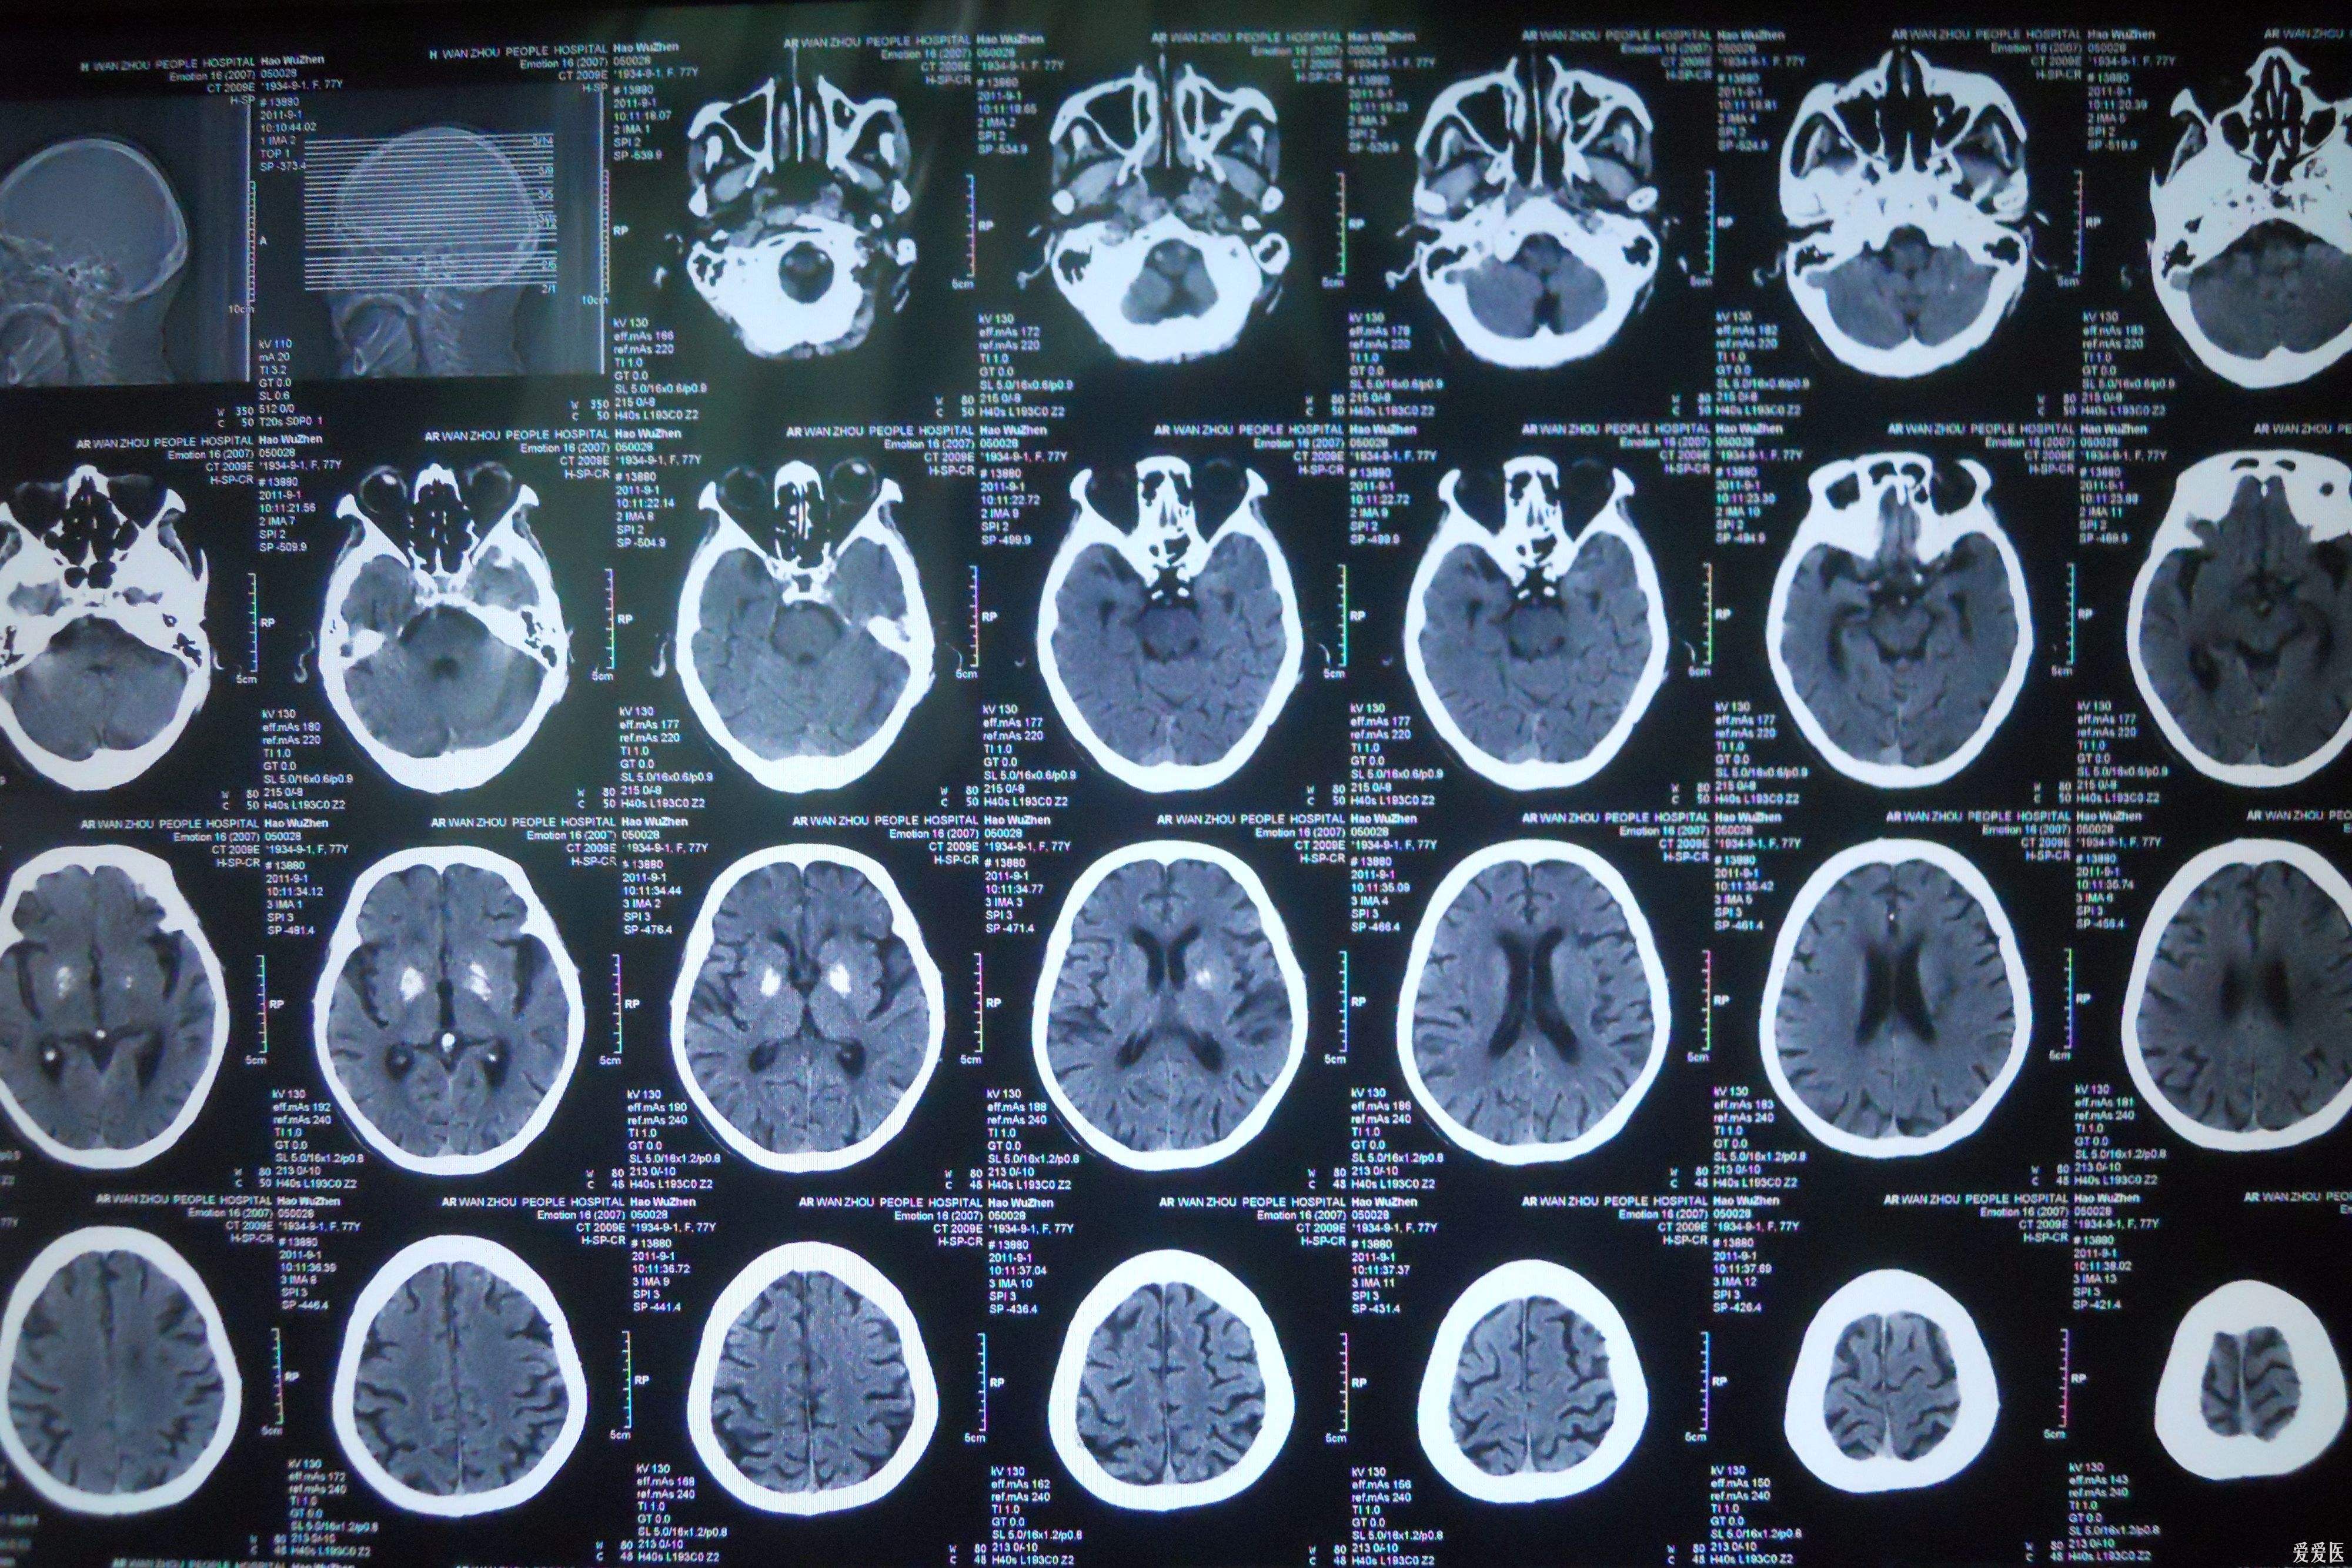

CT和MR照出来的片子,都是由数十个小格图片组成,小格里面是黑白灰色构成的人体横截面图,就像把包子切成一片片,观察里面是什么“馅”。事实上,两种检测的成像原理天壤之别。

由于血液的密度比脑组织高,CT容易分辨,所以当怀疑脑外伤或脑出血时,第一时间进行CT检查,可以发现颅骨是否骨折,脑组织有无出血,及时救治。

对于脑梗塞,MR可以轻易分辨坏死脑组织和健康脑组织,即使是梗塞早期,CT看不出任何变化时,它都能清楚显示,因此是早期诊断的重要依据。另外,对于诊断脑肿瘤、颅内动脉瘤、动静脉血管畸形等颅脑常见疾病非常有效,同时对腰椎椎间盘后突、原发性肝癌等疾病的诊断率也很高。